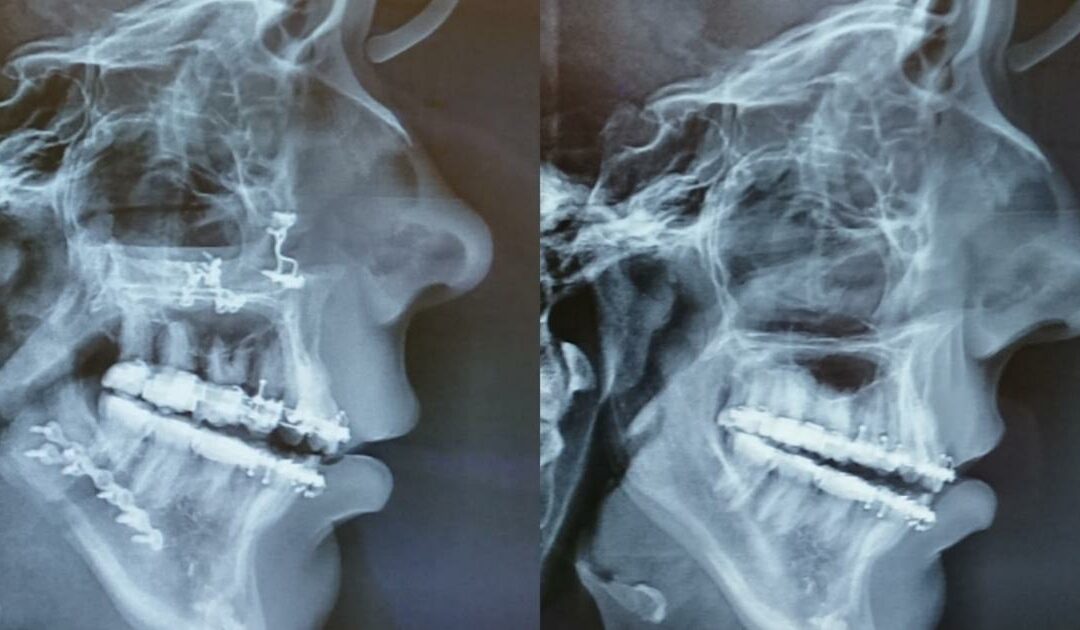

Sarah Steeman over haar bovenkaak verbreding en dubbele kaakoperatie

In dit blog het verhaal van Sarah Steeman. Sarah heeft twee operaties gehad: een bovenkaakverbreding (sarpe) en een jaar later een dubbele kaakoperatie. Ze vertelt hoe ze dit traject heeft ervaren en welke must haves handig zijn tijdens de herstelperiode. Ook deelt ze...